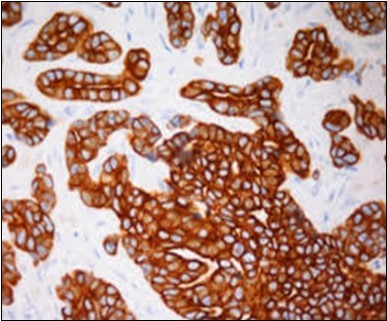

Granular arrangement of malignant cells and intercellular bridges are conspicuous with the demonstration of nuclear atypia, pleomorphism, prominent mitosis and tumour necrosis. A peripheral palisade is discernible within the cellular aggregates. Mitotic figures are common and can be quantified as up to 12 mitosis/ high power field. Tumour differentiation can prominently be of the ductal category with the demonstration of intra-cytoplasmic lumina. Comedo type tumour necrosis is evident along with foci of squamous differentiation The neoplasm is reactive to periodic acid Schiff ‘s (PAS) stain. (Figure 1, Figure 2, Figure 3, Figure 4, Figure 5, Figure 6, Figure 7, Figure 8, Figure 9, Figure 10, Figure 11, Figure 12, Figure 13.

Figure 12.Immune reactivity to cyto-keratin (CK7) in eccrine porocarcinoma(24).

Figure 13.Immune reactivity to CK6 in eccrine porocarcinoma(25).

Eccrine porocarcinoma is immune reactive to carcino-embryonic antigen (CEA) and cyto-keratins 6 and 7(CK6,7), epithelial membrane antigen (EMA) and non reactive to S-100 protein. Reactivity to cyto-keratin 20 (CK20) assists the diagnosis in instances with indeterminate histology. Immune reactive p63, CK5 , weak P40 and non reactive GATA3 are additionally elucidated by the tumour 2, 3, 4.